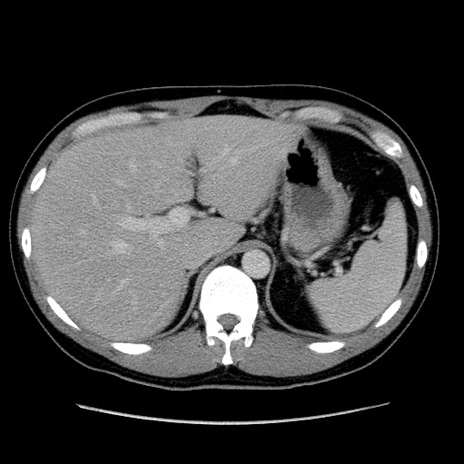

冠状断像